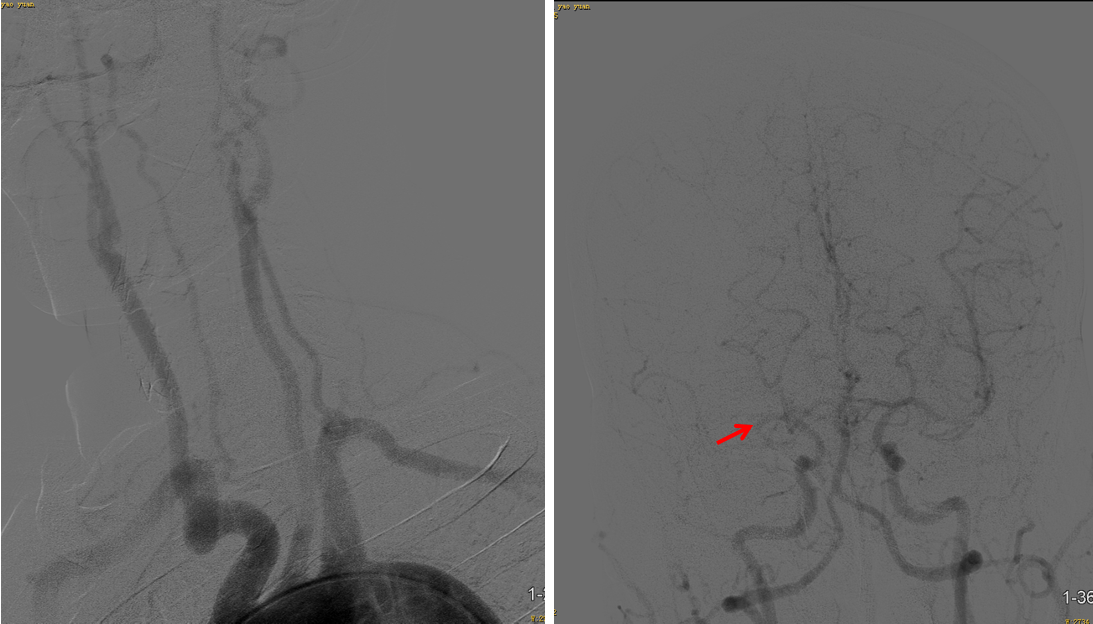

事件:M1中远段闭塞

策略:支架取栓

技术:SWIM

病因:心源性栓塞。

原因:血栓质韧。

方式:支架取栓。

该病例是心源性栓塞,血栓质韧,本例选用蛟龙4*30mm更长的取栓支架,更长长度提供更大表面积接触血栓,以独特的侧边螺旋开放结构,帮助快速高效一次三级再通。一篇研究回顾性分析了2011年6月到2017年3月使用直径4mm取栓支架及球囊指引导管作为首选治疗策略治疗ICA、MCA急性闭塞的病例。该研究中,4×30mm和 4×40mm被定义为长支架,4×20mm被定义为短支架。主要的临床结局是一次性取栓血管成功再通率(mTICI 2b/3)。研究共纳入420例患者,其中221例(53%)患者使用长支架,119例(47%)使用短支架。相对于短支架,长支架组一次性取栓血管开通率(62% vs 50%;P=0.01)和最终血管开通率(mTICI2b/3,98% vs 94%;P=0.01)更高。长支架一次性取栓成功开通率高的原因,可以从以下几方面来解释:长血栓会提供更大的表面积与取栓支架接触包裹血栓,也会在取栓过程中使张力均匀分布,在血管路径扭曲或者躁动的病人中,长支架通过增加可接受的误差范围来实现精确释放。更长的支架会增加取栓装置向血栓远端延伸的移动力,同时,在支架首个与血栓接触的网孔抓捕血栓失败的情况下,可以增加血栓取出的机会。[1]因此,通桥医疗即将上市的蛟龙4*30mm取栓支架在临床上的广泛应用值得期待。